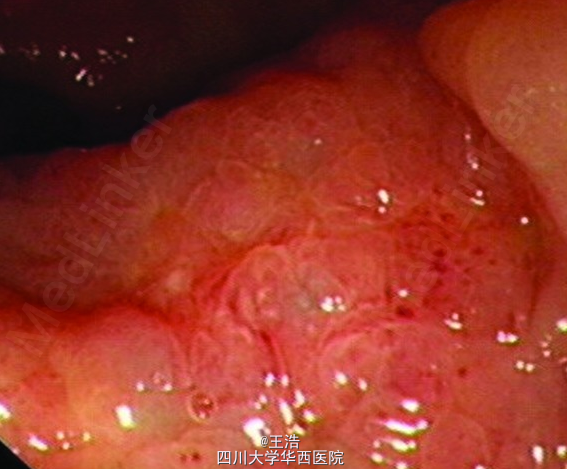

患者术后随访20个月。胸膝卧位检查,可触及距肛门约2.5cm一菜花样新生物。盆腔MRI可见直肠壁增厚,在前列腺与输尿管底部之间可见一肿块。盆腔CT未见淋巴结受累,腹部胸部CT也正常。初步诊断为直肠癌。

遂行直肠镜活检,提示低分化腺癌。免疫组化提示PSA(+), CK20(-), CDX2(-), Villin(+) ,P504S(+)。通过既往史以及目前的资料分析,患者直肠腺癌可能与前列腺癌有关。遂建议患者行新辅助化疗,以便进一步手术治疗。